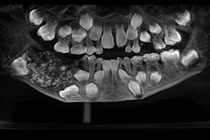

Khi chỉ định chụp X-quang, bác sĩ phát hiện xương hàm dưới có khối u răng kích cỡ 3x4 cm, bên trong chứa nhiều răng to, nhỏ có đầy đủ tổ chức như rằng bình thường, kết lại thành một khối.

| Khối u răng của nam bệnh nhân chứa đầy răng to, nhỏ phía trong. |